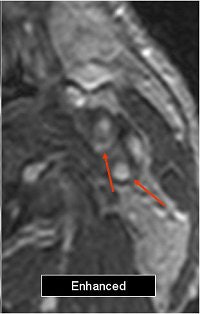

Electronic subtraction (unenhanced minus enhanced axial images) was performed. Internal carotid stenoses were graded on maximum intensity projection (MIP) and multiplanar reformatted (MPR) coronal images. North American Symptomatic Carotid Endarterectomy Trial (NASCET) criteria were applied to judge the percentage of stenosis.

Plaque enhancement was evaluated on axial images by two radiologists in consensus on a four-point scale (0 equaled no enhancement; 3 equaled clear enhancement). They looked at enhanced, unenhanced, and electronic subtraction images.

The results showed that in 92 carotids mild stenosis was found in 29 segments (NASCET 32%), moderate stenosis in 39 (42%), and severe stenosis in 24 (26%). Plaque enhancement was detected in eight of 46 patients and in nine of 92 carotids. The degree of stenosis in these cases was mild (22%), moderate (67%), and severe (11%).

The mean score for plaque enhancement on unenhanced and enhanced images was 1.44. On subtracted images, the mean score was 2.44.

![]() |

| Above, the unenhanced image. Below, the enhanced image and the MRA showing plaque enhancement, which is more evident after electronic subtraction. All images courtesy of Dr. Francesco Sardanelli. |